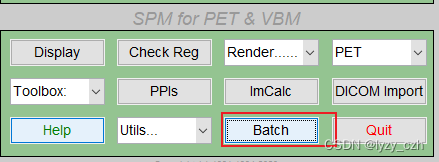

1) 打开matlab命令行输入spm pet,打开SMP12,界面如下

1、点击Batch